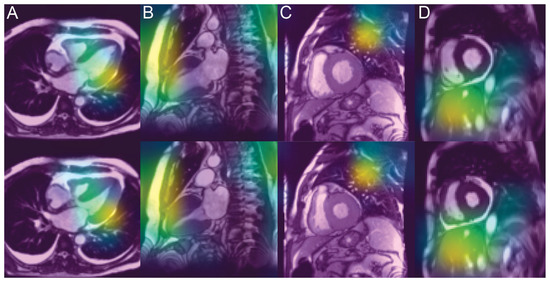

3.4. Analysis of the Saliency Maps

4.3. Unveiling the Invisible

4.4. Explanation of Classification Remains Unsatisfactory